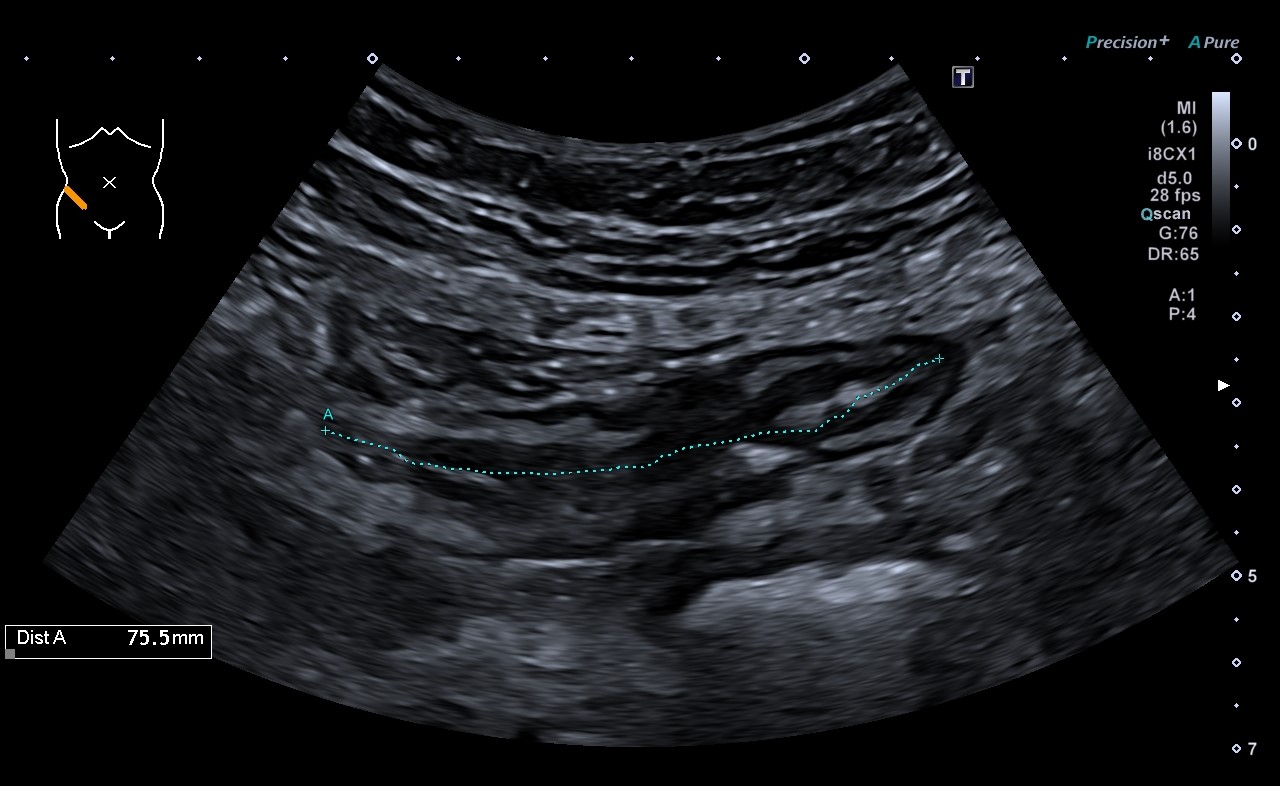

Ecografía intestinal: con la obtención ecógrafos de nueva generación y de sondas de alta frecuencia, podemos evaluar el tubo digestivo, por lo que estamos usando esta ventaja para el diagnóstico, evaluación y seguimiento de pacientes con enfermedad inflamatoria intestinal.